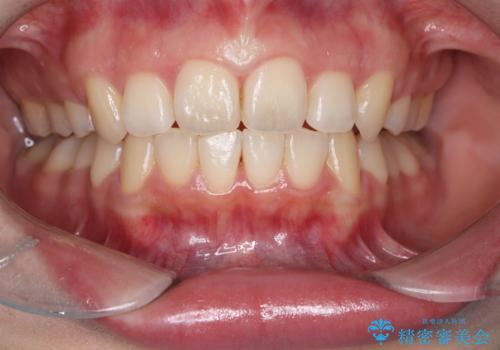

矯正後のホワイトニング希望

- 矯正治療が終わり歯並びも綺麗になったので黄色い歯を白くしたくなったようです。

歯並びや歯が綺麗になり笑顔も更に素敵に患者さまも喜んでいられました。

オフィスホワイトニングのブースト使用